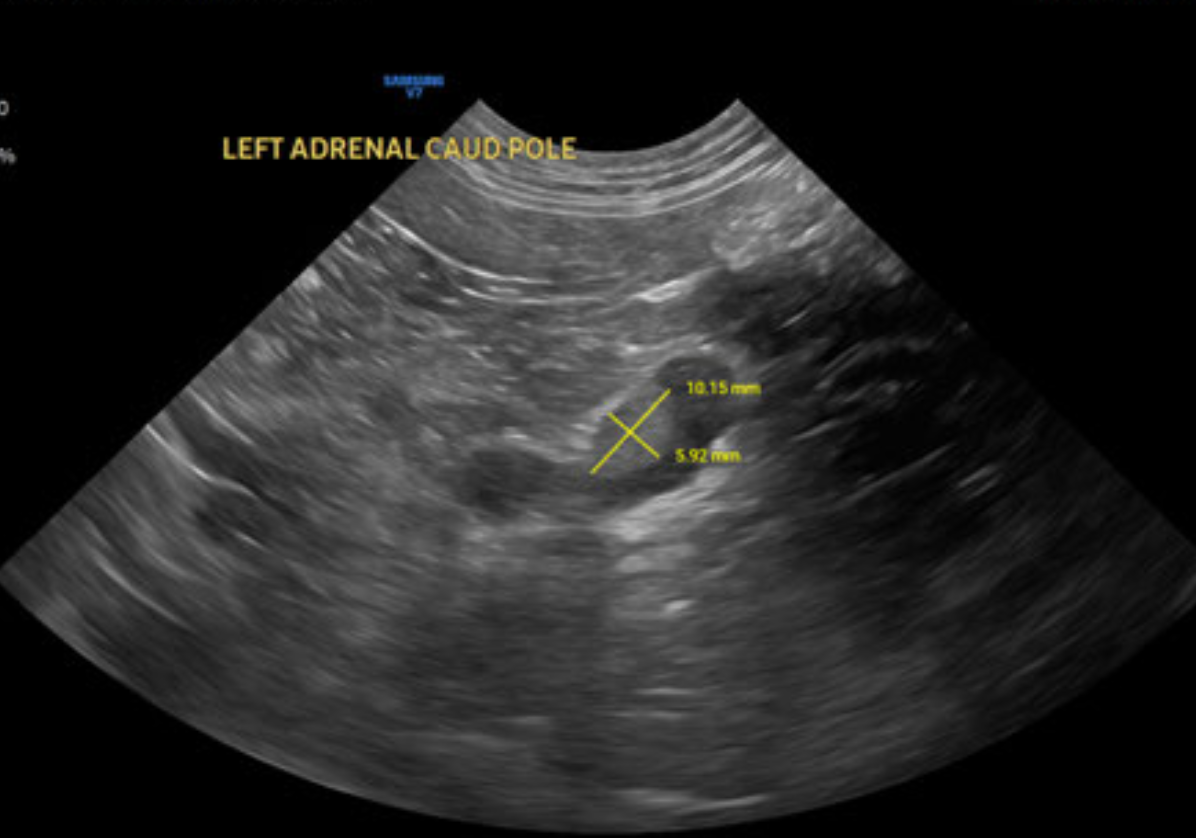

Dr. Kenny Siu, DVM, DACVIM (SAIM) reviewed a full abdominal ultrasound and provided an in-depth internal medicine consultation.

Ultrasound findings included:

• Cystic chronic renal changes

• Hepatomegaly with mild cholecystic debris

• Generalized small-intestinal ileus

• Left adrenal nodule

• Mild pancreatic heterogeneity

No primary abdominal cause for the seizures was identified and no evidence of abdominal neoplasia was noted.

Dr. Siu’s consultation integrated metabolic, endocrine, and paraneoplastic differentials—including insulinoma, iatrogenic hypoadrenocorticism, and Cushing’s-related vascular disease. He recommended ACTH stimulation, paired insulin : glucose levels, blood-pressure monitoring, and tailored fluid and electrolyte therapy, as well as provided seizure-management recommendations.